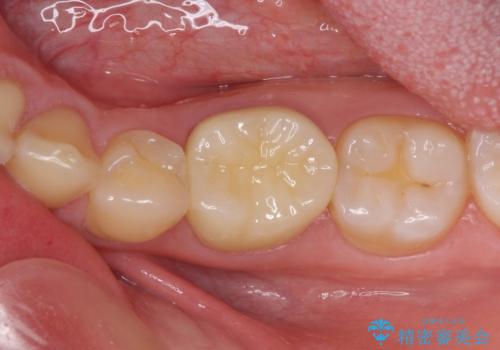

むし歯が大きく、神経を取り除く可能性があることを理解いただいた上で虫歯を取り除き、その後はオールセラミッククラウンにて補綴することとしました。

虫歯除去後に痛みは収まり、神経も保存することができました。

変色していた歯もセラミッククラウンで自然な色合いとなり、患者様には大変満足していただきました。